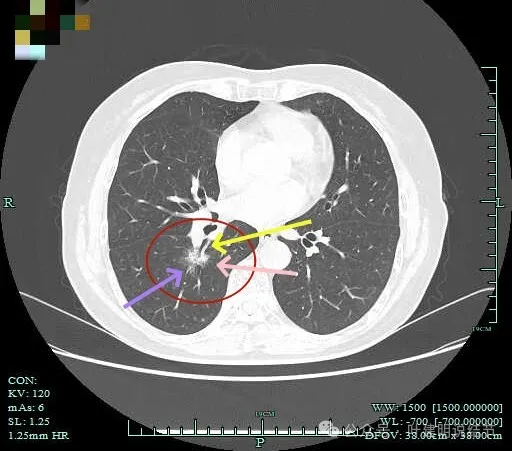

边缘有毛刺征!

沿支气管走行方向延伸,磨玻璃密度,且支气管内壁显得毛糙。

毛刺明显,轮廓清楚,灶内支气管扩张通气。

毛刺明显,灶内有实性成分出现。

毛刺征明显!!灶内密度杂乱。